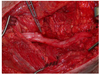

Which of the following conditions is a relative CONTRAINDICATION for use of the flap in the image shown for reconstruction of an 8 x 10-cm anterior ankle wound?

The correct response is Option D.

Hypertension does not preclude the use of any fasciocutaneous flaps in the lower extremity.

Diabetes mellitus can be associated with peripheral vascular disease, but by itself, would not prevent successful use of the reverse sural artery flap for foot or ankle reconstruction. Appropriate preoperative workup would include noninvasive ultrasound study of the lower extremity vasculature to prove the peroneal artery was patent.

Vascularized flaps, including the reverse sural artery flap, provide excellent coverage for foot/ankle wounds, including those with underlying osteomyelitis. Effective treatment would necessitate adequate debridement and antibiotic therapy as part of the reconstructive paradigm.

The distally based sural artery flap receives its blood supply from a few sources, the most robust of which are perforators from the peroneal artery. The most distal of these perforators arise between 4 and 7 cm proximal to the lateral malleolus. Additional perfusion arises from neurocutaneous perforators from the sural nerve and venocutaneous perforators from the lesser saphenous vein.